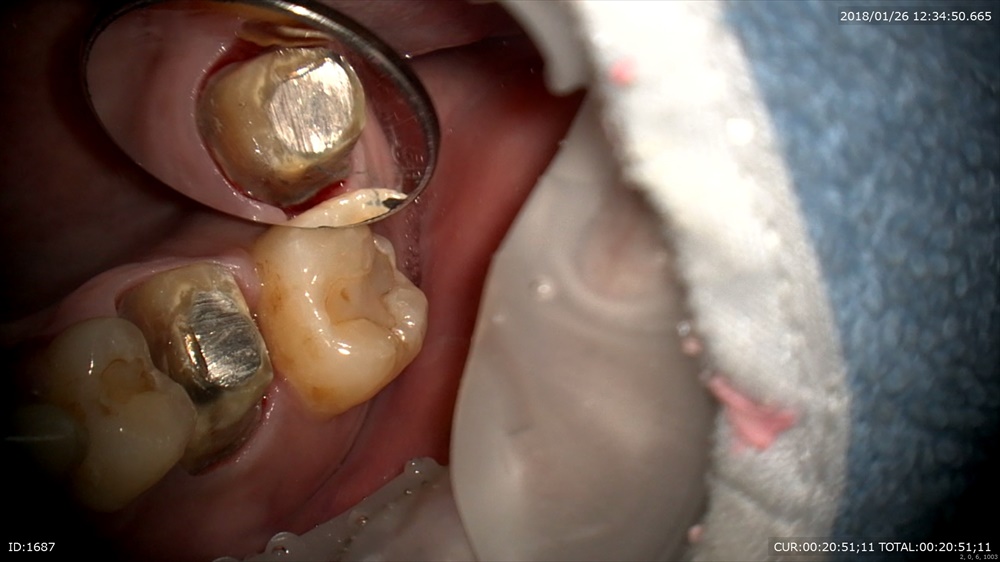

次の方。一見ちょっと黒いけど。。。。歯科ドックで発覚しました。この下にむし歯があります。

ギャー!!!ドックやってよかった。

神経に近い所はMTAセメントで

二層目

マイクロスコープで直視できます。ピコモラー最高!!